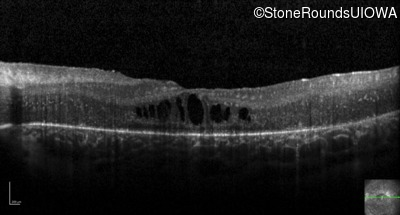

Optical Coherence Tomography - Right - 20/80 -1

Exemplar / OCT Stack

Optical Coherence Tomography - Left - 20/125 +2